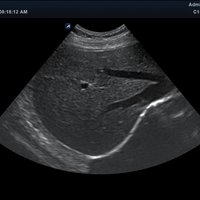

Das Alpinion minisono ist ein tragbares Hand-Ultraschallgerät, das eine sichere und schnelle Diagnostik u. a. in den Anwendungsbereichen Abdomen, MSK, Vaskulär, kleine Organe sowie Bauch und Brust bietet. An das minisono kann über USB-Kabel entweder eine Linear-Sonde oder eine Konvex-Sonde angeschlossen werden. Die komplette ultraschallspezifische Hardware ist in den Griffstücken integriert.

• Abdomen

Anwendungsbereiche Abdomen MSK, Nerven, Karotis, periphere Gefäße, Schilddrüse, Mamma

Bildgebungs-Modi B-Modus, CF, M, PW, PD B-Modus, CF, M, PW, PD

• B-Modus: Darstellung zweidimensionale Bilder anatomischer Strukturen